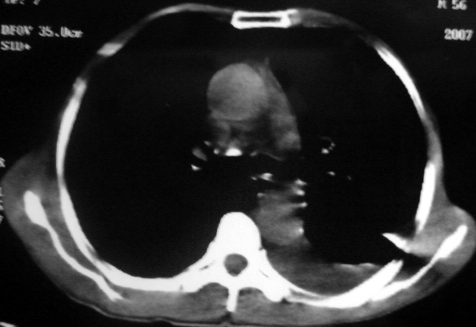

男,54岁,咳嗽,气喘半年,胸痛一月.

血性胸水

1.左肺下叶中心性肺癌伴阻塞性肺炎,肺不张.

2.左侧胸腔积液,心包积液